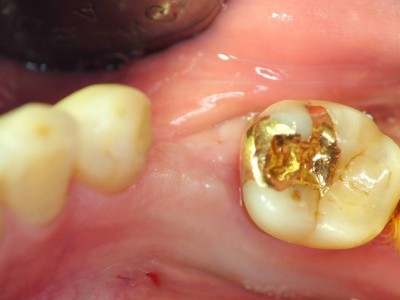

A+ 임플란트의 다양한 케이스를 확인해보세요.